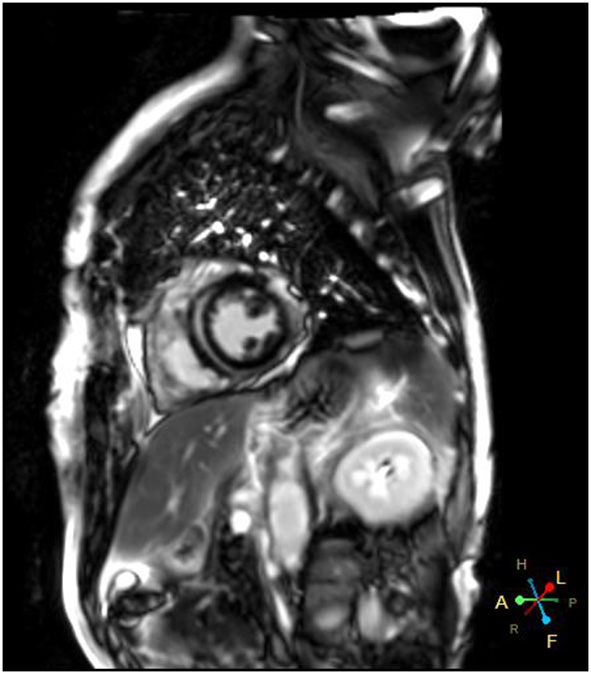

A 66-year-od man with advanced lung adenocarcinoma was admitted to the local chest pain center with progressive chest pain, dyspnea. He had been diagnosed with advanced lung adenocarcinoma 4 month earlier. He had no history of autoimmune or cardiovascular diseases. Cardiac screening tests including cardiac biomarkers, ECG (Figure 1), and echocardiography showed normal results before chemotherapy. The patient was treated with four cycles of albumin paclitaxel plus carboplatin. The CT scan showed that the patient was not responding to chemotherapy. Then he started albumin paclitaxel plus carboplatin for chemotherapy combined with sintilimab (200 mg/injection). 3 weeks after sintilimab initiation, the patient presented with chest pain, shortness of breath and was admitted to the hospital. His vital signs were unstable on arrival (temperature 36.7°C, heart rate, 84 beats/min; respiratory rate 17 breaths/min, blood pressure 84/52 mmHg. The admission ECG showed sinus rhythm with ST-segment elevation in leads V5 through V9 (Figures 2, 3); laboratory test showed that cardiac troponin-I was 9.4 ng/mL (normal range, 0.00–0.03 ng/mL), CK 922IU/L (normal range, 22-270IU/L), CK-MB 109 IU/L (normal range, 2-25 IU/L);NT-proBNP 8290pg/ml (normal range, 0-349pg/ml). Transthoracic echocardiography showed anterior hypokinaesia, severe left ventricular function impairment with a left ventricular ejection fraction of 35%, mild pericardial effusion (Supplementary Videos 4–7). Coronary angiography was performed showing normal coronary arteries (Supplementary Videos 1–3). A diagnosis of sintilimab associated myocarditis was considered. The patient received methylprednisolone (2 mg/kg) and immunoglobulin (0.4g/kg/d) intravenously for 7 days. At day 4, the ECG showed that the elevated ST-segment had fallen back (Figures 4, 5). At day 8, cardiac magnetic resonance was performed and showed late gadolinium enhancement in the mid layer of the septal segment and the subepicardial layer of the inferolateral wall (Figure 6), with an ejection fraction of 47% (Supplementary Video 11). Gradually, the patient's symptoms improved and his vital signs were stable. The lab tests showed persistent decrease of hs-cTnI, myocardial enzyme indexes (Table 1). Echocardiogram revealed improved left ventricular systolic function, with an ejection fraction of 52% (Supplementary Videos 8–10). The dose of glucocorticoid therapy was gradually reduced. The patient was discharged 10 days after admission. He received oral prednisone tablets with gradually decreasing doses and regular follow-up.

Figure 6

Cardiac magnetic resonance showed late gadolinium enhancement in left ventricular wall.

In recent years, Immune checkpoint inhibitors has become more widely used in clinical practice and improved the prognosis of patients with malignancy. In the meantime, ICI have been reported to induce cardiovascular toxicities, including myocarditis, pericarditis and vasculitis. The incidence of ICI related myocarditis has ranged from 0.27 to 1.14% (9), but it is often severe and life threatening. The reported incidence of ICIs-related myocarditis is low (<1%), it can be life threatening with a mortality rate up to 60 % (10, 11). Endomyocardial biopsy remains the gold standard for definitive diagnosis of ICI-induced myocarditis but it is not widely used because of its procedural risks and technical limitations. Cardiac magnetic resonance (CMR) has evolved as an standard noninvasive tool for the diagnosis and evaluation of myocarditis. Late gadolinium enhancement (LGE) is associated with a poor prognosis in patients with ICI-induced myocarditis (12). Myocardial biopsy and CMR are often not available in the setting of an acute presentation. It has been demonstrated that 2D/3D speckle-tracking strain imaging echocardiography may be promising diagnostic and prognostic tool in acute myocarditis, even in patients with preserved left-ventricular ejection fraction (13). However, the major pitfalls of speckle-tracking are its dependency on image quality and its ability to define the endocardial and epicardial boundaries. Once diagnosed, treatment should be initiated immediately. However, due to the absence of high-level evidence studies, there are still no standard therapeutic strategies. Glucocorticoid treatment is recommended for ICI-associated myocarditis but the effective dosage and optimal duration of corticosteroid therapy are not precisely recommended. Due to limited clinical data, the utility of other immunosuppressive agents is not well established.

Sintilimab is a humanized monoclonal IgG4 antibody which was approved for the treatment of hematological cancers and several advanced solid tumors in China. The epitope of the sintilimab/PD-1 complex is located at the FG loop of PD-1, which is different from that of nivolumab or pembrolizumab Compared to nivolumab or pembrolizumab, sintilimab has a higher binding affinity with more PD-1 molecules on CD3+T cells, and has better T cell activating characteristics. Sintilimab exhibited good safety and tolerability in clinical studies (5–8). Compared to nivolumab or pembrolizumab, sintilimab has a higher binding affinity with more PD-1 molecules on CD3+T cells, and has better T cell activating characteristics. For sintilimab, the incidence of fatal treatment-related adverse events (TRAEs) ranges from 1 to 6.25%. The incidence of TRAEs for sintilimab monotherapy ranges from 0 to 2.5%. It seems to be higher than average (14). Four cases of sintilimab-induced myocarditis have been reported recently (15–18), but cardiac magnetic resonance imaging was not performed in all of these patients. In our case, the echocardiography showed that cardiac function was severely damaged with a LVEF of 35% on admission. A significant improvement of left ventricular systolic function with a LVEF of 52% was noted several days after treatment. However, cardiac MRI showed extensive myocardium fibrosis. Therefore, longer follow-up is warranted to determine whether myocardial fibrosis can fully regress and to observe the the long-term prognosis of the patient.